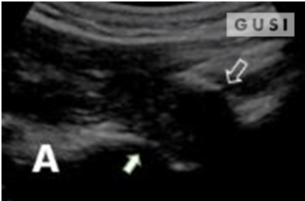

During the 2018 World Taekwondo Junior Championships in Hammamet, Tunisia, a 17-year-old male junior Taekwondo athlete took a fall, landing on his right shoulder. He exhibited a markedly limited range of motion in the affected shoulder and experienced intense pain, leading to suspicions of a dislocation.

A pre-reduction ultrasound (A) of the right shoulder showed a pronounced gap between the humeral head (indicated by a solid arrow) and the glenoid (marked by an open arrow), suggesting an anterior dislocation. Following a shoulder reduction procedure, a post-reduction ultrasound (B) verified the successful realignment of the glenohumeral joint (solid arrow pointing to the humeral head and open arrow to the glenoid).

After the procedure, the athlete displayed a considerably improved range of motion in his right shoulder and his pain levels diminished significantly.